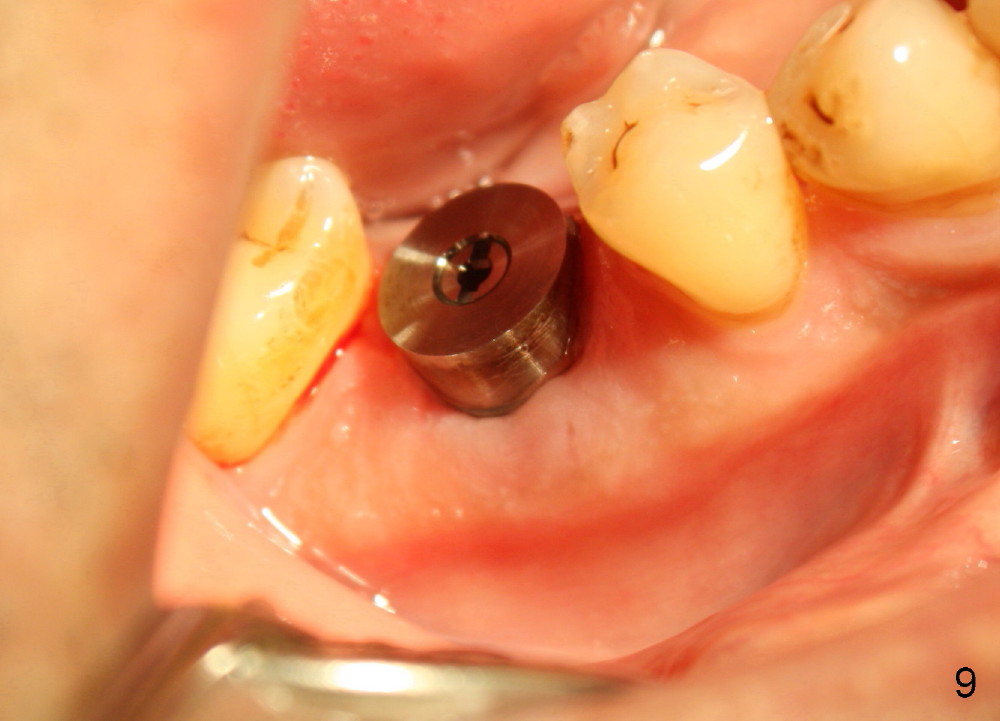

The distal socket is closed completely with suture, whereas the mesiobuccal space is partially closed with collagen gauze and suture (Fig.8 *). The wound is then covered by perio dressing. The gingiva heals around the implant 18 days postop (Fig.9). Three months postop, the implant is stable. The mesial upper portion of the threads appears to have better contact with the bone (Fig.10 <, as compared to Fig.7); the density of the distal socket seems to increase (*). There is no buccal plate atrophy (Fig.11 ^). Supragingival margin is designed for the crown to prevent periimplantitis (Fig.12)